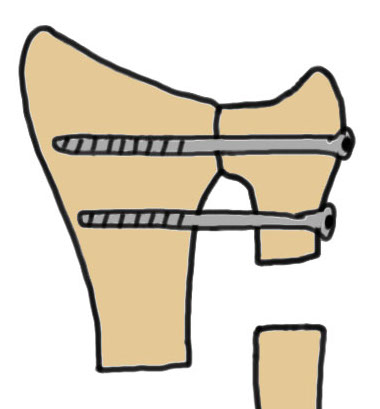

Suave-Kapanji distal radio-ulna arthrodesis

Technique

Distal radio-ulna arthrodesis with screws + proximal ulna pseudoarthrosis

Dorsal approach

- between ECU and EDM (extensor compartment 5 and 6)

- protect dorsal sensory branch of ulna nerve

- open extensor compartment

- proximal ulna osteotomy and resection 1 cm to allow rotation

- debrided lateral ulna and sigmoid notch of radius

- radioulna arthrodesis with screws

- interposition with pronator quadratus to create proximal ulna pseudoarthrosis

- +/- stabilized with slip ECU / FCU to prevent proximal ulna instability